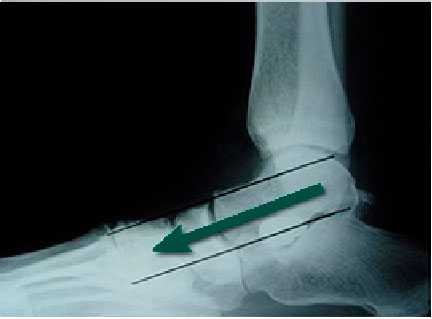

Артроэрез

При дисфункции сухожилия задней большеберцовой мышцы большой эффективностью отличается операция артроэрез. Операция не требует больших разрезов и хорошо переносится пациентами.

![артроэрез ход операции]()

При артроэрезе введенный между пяточной и таранной костью имплант ограничивает наружное отклонение пяточной кости, в связи с чем не происходит проседание свода стопы при ходьбе.

Предложено несколько типов имплантов из разных материалов для артроэреза. У взрослых эта операция редко выполняется как самостоятельное вмешательство. Для коррекции деформации и стабилизации стопы в правильном положении артроэрез обычно дополняют и другими корригирующими вмешательствами (например по перемещению сухожилий).